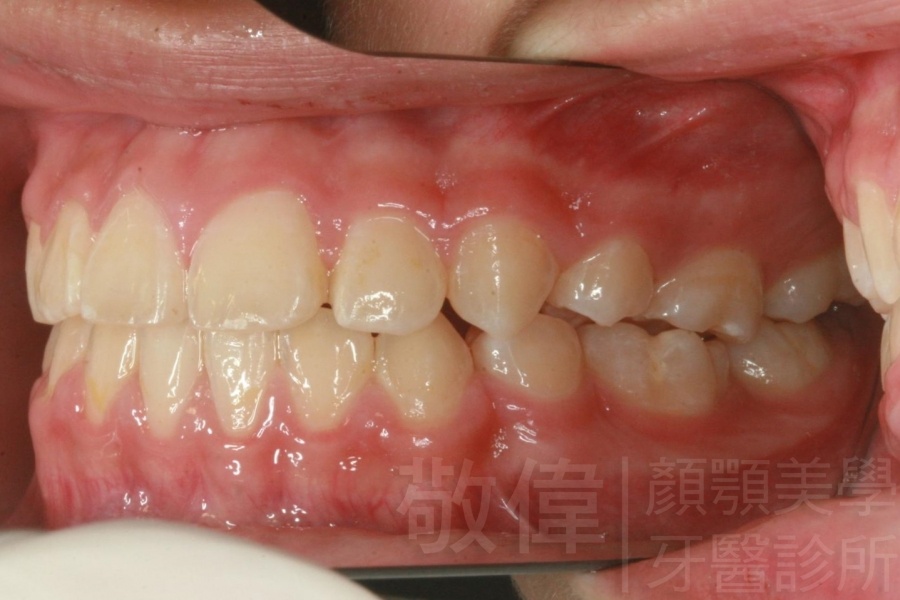

齒顏矯正/上顎暴牙且牙齒極度混亂

矯正前-右   矯正前-正   矯正前-左

矯正後-右   矯正後-正   矯正後-左

<個案說明>

上顎暴牙且牙齒極度混亂,經由矯正之後,臉型大幅度改善,牙齒的排列更加的整齊健康。相較於之前眼神充滿精神,自信心展現無遺。